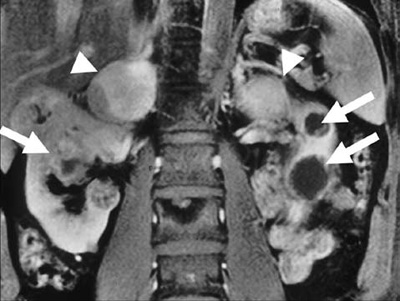

We distinguish two major subgroups of VHL Syndrome: VHL type 1 mainly without and VHL type 2 mainly with pheochromocytoma presentation.32 The clinical features of the VHL syndrome include retinal (von Hippel) and cerebellar (Lindau) hemangioblastoma, as well as brainstem and spinal hemangioblastoma. They also include presence of renal cysts and renal cell carcinoma, pancreatic cysts and islet cell tumours, endolymphatic sac tumours, as well as cysts and cystadenomas of epididymis and broad ligament (Figure 1).

Figure 1. Sagittal MRI section shows bilateral cystic renal cell carcinoma (arrows) and bilateral adrenal pheochromocytoma (arrow heads) in a patient with von Hippel-Lindau disease.

The VHL gene lies on the short arm of chromosome 3 (3p25), with 3 exons coding for 2 isoforms of the protein.33 The mutations are spread in all three exons. Missense mutations, usually confer better prognosis and are more frequently detected in patients presenting with pheochromocytoma.34 About 20-30% of VHL type 2 patients develop a pheochromocytoma. The age at diagnosis is younger than in sporadic cases. They are frequently multiple: bilateral adrenal and multifocal extra-adrenal. Rarely, they are malignant.